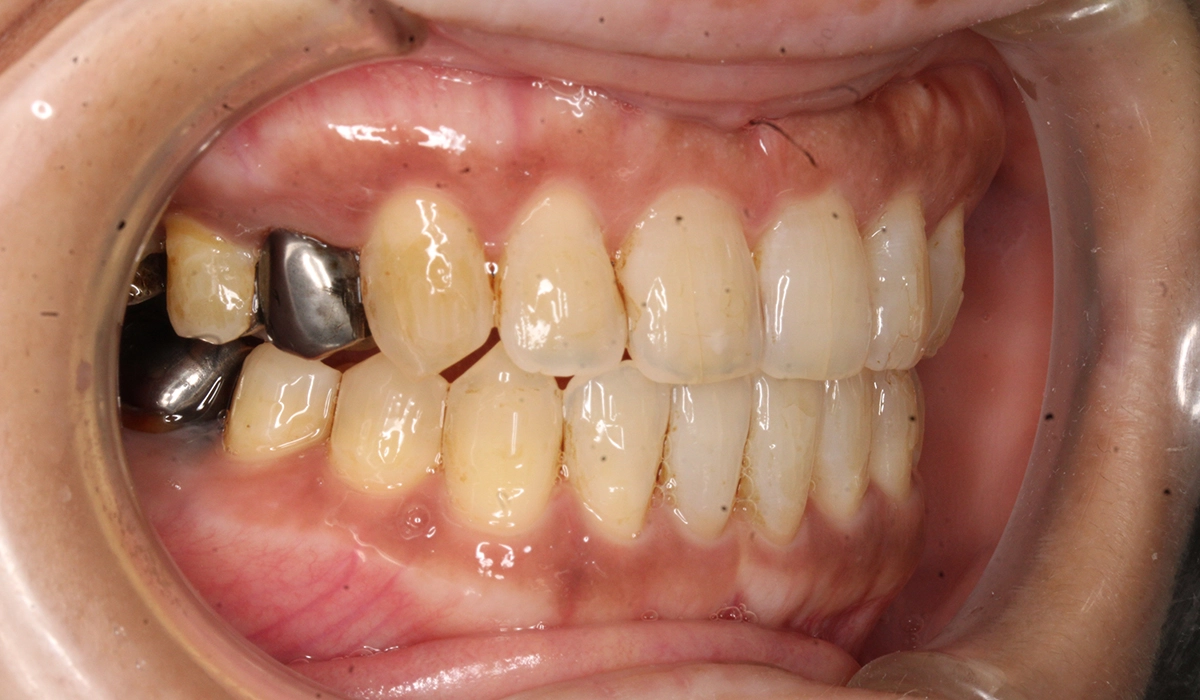

術前:左側